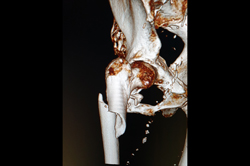

Total Hip Replacement - THR

Periprosthetic Fracture THR